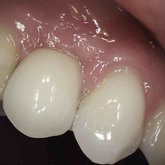

Porcelain crowns and restorations made in one appointment.

We make it a priority to incorporate the latest in dental technology in everything we do at our practice. ...